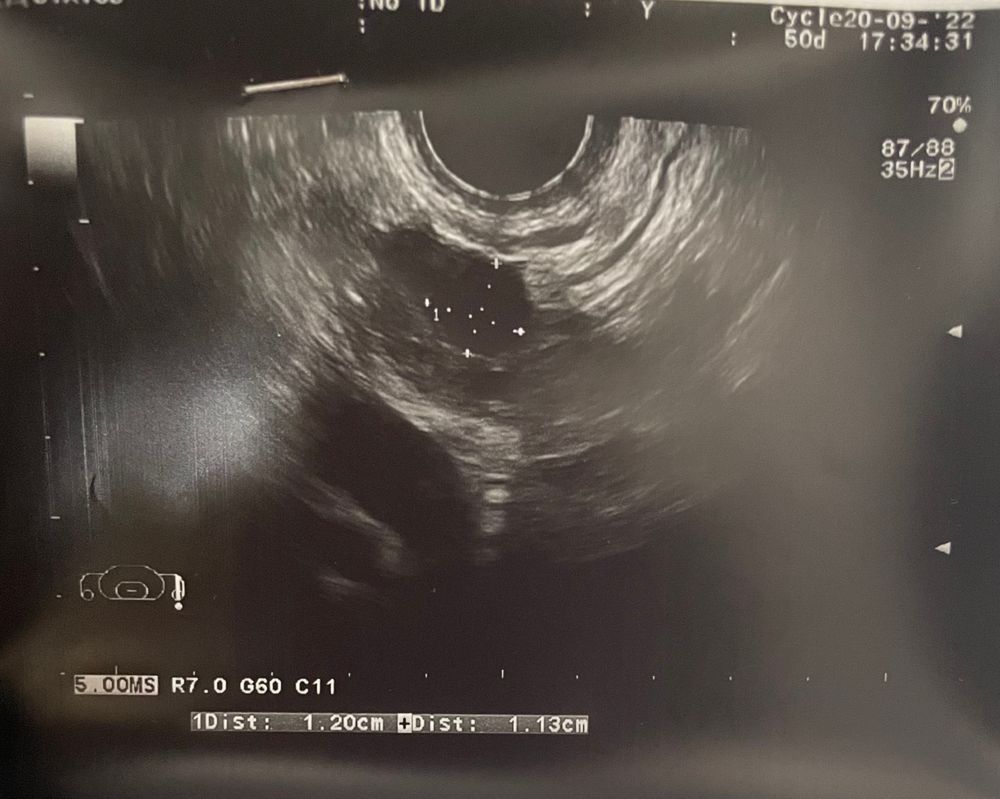

Что-то у меня есть подозрения что это никакой фоликул…

Прошлый месяц был ановуляторный, мес пришли в срок. Макс фоликул 12*11

Этот месяц(ниже) узистка говорит, это фоликул скоро лопнет. Но мне непонятно, что у него внутри там что-то. Посмотрела по бб- как будто бы это киста? Она на том же месте что и в прошлом месяце. Вам тоже кажется что что-то не то?

Alinnas, киста образовывается Из-за того что дф не смог лопнуть (гормона не хватило), и этот фолликул образовался в кисту. На первом узи фолликул, на втором уже из этого фолликула киста. Но , что меня смущает, фоликул должен достичь размера 20-23 мм что бы лопнуть, а тут какие-то маленькие размеры. А зачем знать что внутри?